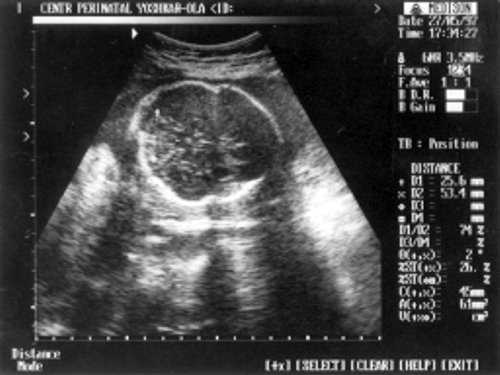

Данные фетометрии:

- (бипатериальный размер головы - от виска до виска) = 65 мм - 26 нед.,

- ОкГ (окружность головы) = 244 - 26 нед. + 3 дня.

- МРМ (межполушарный размер мозжечка) = 25,6 мм - 23,5-24 нед. (рис. 1)

- ОкГрК (окружность грудной клетки) = 42 мм - 19,5 нед.

- ОЖ (окружность живота) = 182 мм - 22 нед. + 6 дн.

- ДБ (длина бедра) = 24 мм - 17 нед. (рис. 2)

- Плечевая кость = 16 мм - 14,5 нед. (рис. 3)

- Кости предплечья = 17,5 мм - 15,5 нед. (рис. 4)

- Малая берцовая кость = 22 мм - 18,5 нед.

- Большая берцовая кость = 24 мм - 18,5 нед.

Рис. 1. УЗИ плода - голова.

Рис. 2. УЗИ плода - бедро.

Рис. 3. УЗИ плода - плечевая кость.

Рис. 4. УЗИ плода - кости предплечья.